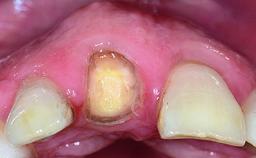

Replacement of a Missing Upper Left Central Incisor: Late Placement of an RC Bone Level Implant, CAD/CAM Zirconia Abutment

Eduardo R Lorenzana, Jason R Gillespie

A healthy 37-year-old female patient was referred for a consultation on the replacement of missing tooth 21 with an implant-supported restoration. She stated that several years previously the tooth had been traumatically avulsed following a motor vehicle accident. The tooth was replaced with a three-unit fixed partial denture (FPD) immediately afterwards. Over time, she became disillusioned with the FPD and looked for a different option, including orthodontic therapy. She presented still in her orthodontic appliances, with the pontic sectioned free from the FPD but attached to the archwire. Her orthodontist felt that orthodontic treatment had been successfully completed, but nevertheless referred her before removing the appliances in case adjustments were necessary.